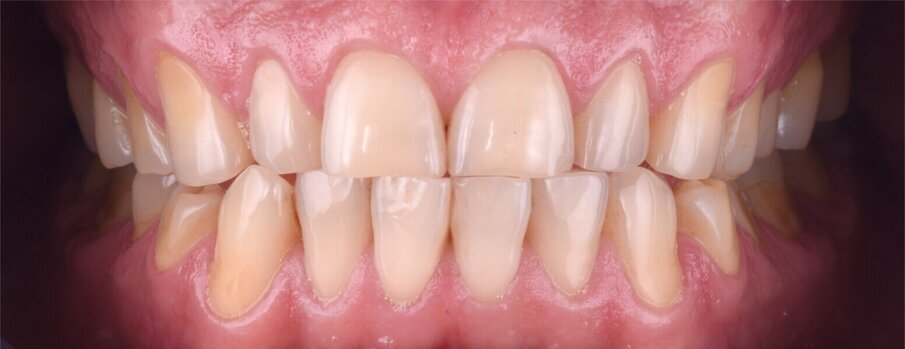

Nakonec byly finální korunkové náhrady (obr. 14) adhezivně fixovány v ústech za izolace kofferdamem (obr. 15). Pacient byl sledován několik týdnů po cementaci náhrad (obr. 16 a 17).

Obr. 17a–c: Finální intraorální fotografie.